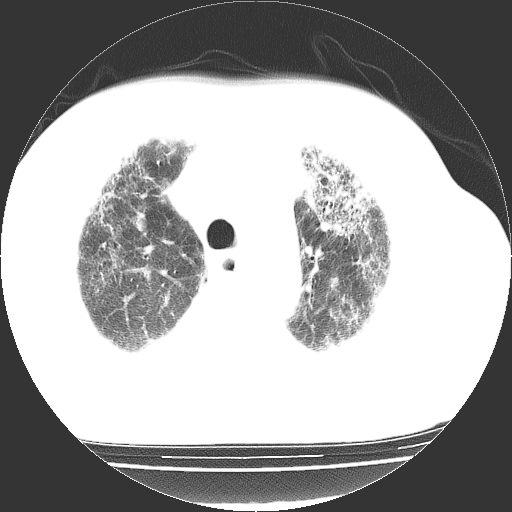

男,68岁,咳嗽、胸闷、发烧三天,查体:双肺散在湿罗音。

首先考虑特发型肺间质纤维化;两侧少量胸腔积液。

依据:1、两肺广泛条索状、网格状、蜂窝状改变。

鉴别诊断:肺结核:病灶呈多形性改变,往往纤维化较多的病例,经常会有空洞;本例不大符合。

慢性支气管炎伴感染:临床病史不大支持,而且往往肺气肿较明显,本例不大明显。

双肺多发条索状、网格状及小灶状密度增高影。考虑慢支合并感染.间质纤维化,双侧少量胸腔积液

两肺广泛条索状、网格状、蜂窝状改变。肺间质纤维化,肺心病,双侧胸腔积液